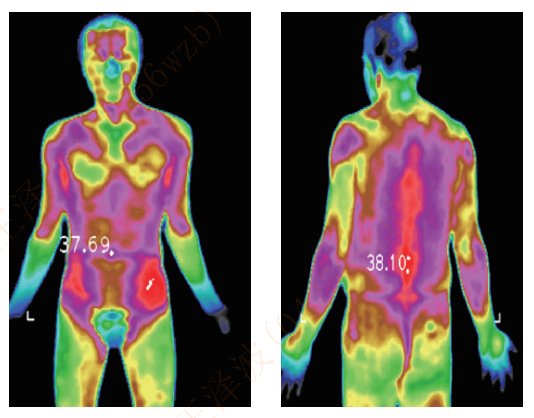

The human body is a natural biological heating element, and its heat radiation implies a lot of health information. Therefore, the change of the human body temperature is one of the important indicators for diagnosing cases. Medical infrared thermal imaging is a whole-body thermal imaging technology that passively receives the heat source of tissue cell metabolism of the human body. It can receive the human body heat radiation that cannot be seen by the human eyes, and objectively and accurately present the temperature distribution images of parts of the body, offering a reliable basis for clinical diagnosis.

Assistance in syndrome differentiation in TCM

It can form the temperature distribution image of the human body by obtaining the infrared radiation signals of different strengths of body parts. It can assist in syndrome differentiation in TCM, physical assessment in TCM, meridian point exploration and treatment effect evaluation. In terms of treatment effect evaluation, it is possible to specify the location, onset time, duration and effect degree of drugs, acupuncture or other treatment methods, objectively and accurately evaluating treatment methods.